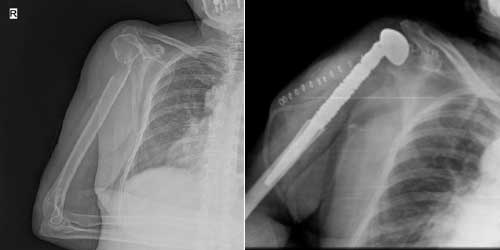

Her ameliyatın olduğu gibi kemik ve yumuşak doku tümör ameliyatlarının da riskleri vardır. Bu riskleri genel ve yapılan ameliyata özgü olmak üzere kabaca iki başlık halinde gruplandırabiliriz. Öncelikle anestezi ile ilgili risklerin anestezi uzmanı tarafından (...)

Ameliyat sonrası takip ve kontrol hastanın ameliyat masasında uyanması ile başlar. Özellikle damar ve veya siniri ilgilendiren ameliyatlarda hasta ameliyat masasından alınmadan ekstremitenin dolaşımı ve ilgili sinirin fonksiyonu kontrol edilir.